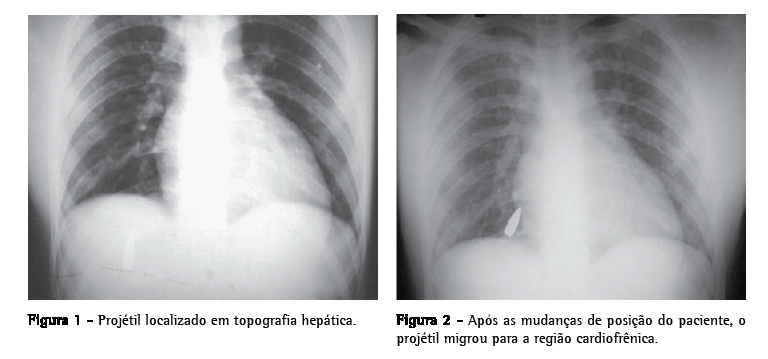

Paciente do sexo masculino, 19 anos, vítima de lesão penetrante por projétil de arma de fogo, deu entrada no serviço de emergência. O orifício de entrada localizava-se no quarto espaço intercostal direito, lateralmente à linha mamilar. Apresentava-se lúcido, eupnéico e hemodinamicamente estável, com mucosas coradas e pulso cheio e amplo. O exame físico não revelou anormalidades. Na radiografia de tórax em incidência póstero-anterior, foi observado um projétil de arma de fogo de alta velocidade (fuzil) localizado em topografia hepática (Figura 1). Com a mobilização do paciente em diferentes decúbitos, a nova radiografia de tórax em incidência póstero-anterior e a tomografia computadorizada evidenciaram a mudança de posição do projétil, agora localizado na região cardiofrênica à direita (Figura 2). Com o diagnóstico de projétil de arma de fogo livre na cavidade pleural, foi indicada a retirada por videotoracoscopia. Após a intubação com tubo orotraqueal de dupla luz e anestesia geral, o paciente foi posicionado em decúbito lateral esquerdo. O procedimento foi iniciado com a introdução de um trocarte de 10 mm e dois de 5 mm. Na inspeção inicial com a ótica de 30°, foram encontrados somente uma pequena equimose no lobo médio e um projétil de arma de fogo livre na cavidade pleural, localizado no recesso cardiofrênico anterior. O mesmo foi facilmente retirado com o auxílio de uma pinça. O paciente permaneceu com o dreno pleural durante 24 h e obteve alta hospitalar no segundo dia de pós-operatório.